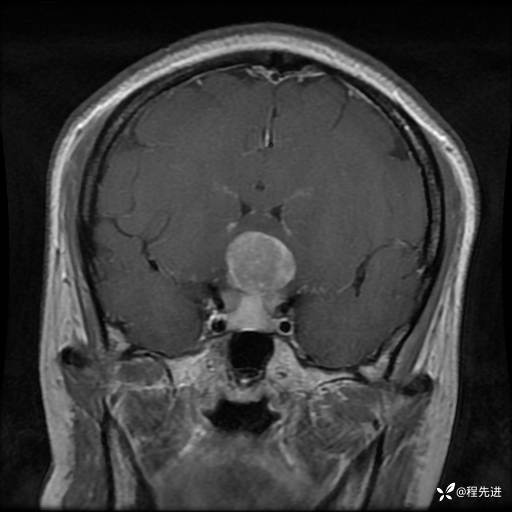

MRI平扫+增强:

T1:

T1+C: